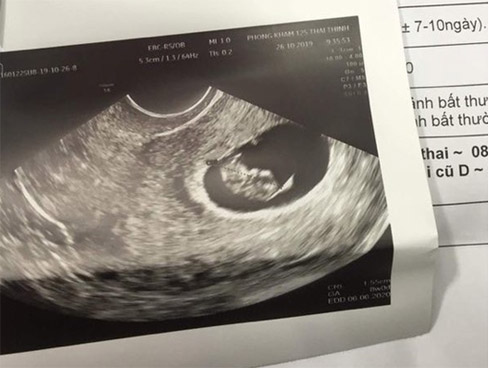

Phiếu siêu âm của bệnh nhân tại một bệnh viện ở Hà Nội.

Đến ngày 27/10, chị A. cùng người thân đến thẩm mỹ viện Sophie International thông báo đã mang thai 8 tuần. Hôm sau, chị được đại diện thẩm mỹ đưa đến Bệnh viện AIH (quận 2) tiến hành thăm khám.

Bệnh viện AIH chẩn đoán bệnh nhân mang thai 8 tuần vào thời điểm ngày 28/10.

Phía AIH xác nhận bệnh nhân có thai, tuy nhiên cho biết với tuần thai trong khoảng 4 tuần rất khó phát hiện thai kỳ dù đã siêu âm, kiểm tra. Lúc này, chị A. và người thân có lời nói xúc phạm đến bác sĩ khám.